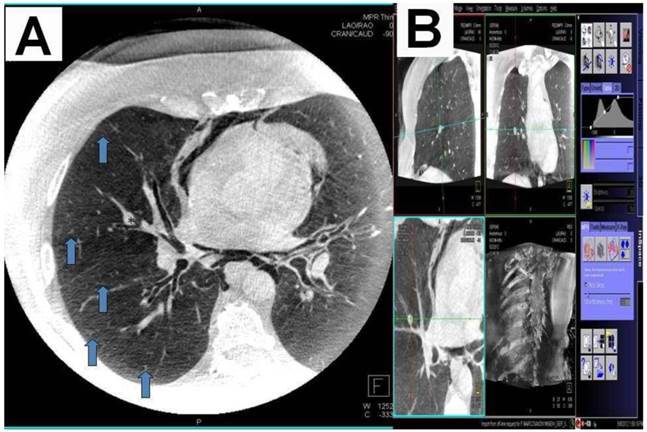

Figure 2

A) DynaCT with carcinoid*Arrows indicating small bronchioli subpleural. B) Right: iguide toolbox with the same dataset before annotation of the path and target volume.